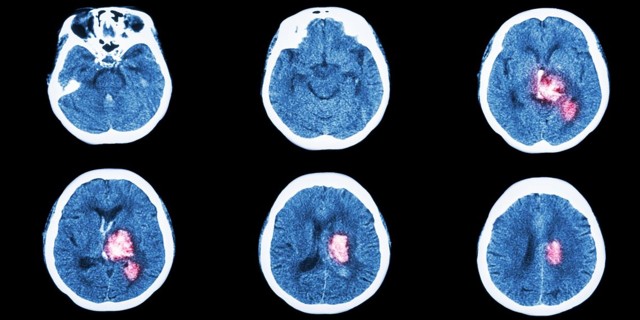

У врачей есть несколько часов, чтобы спасти человека. Симптомы инсульта нужно знать всем, чтобы успеть распознать болезнь. Инсульт — это нарушение кровообращения мозга. Когда кровь не поступает к клеткам (из-за тромба или разрыва сосуда), они погибают. Из-за этого человек утрачивает способности: двигаться, говорить, видеть, дышать.